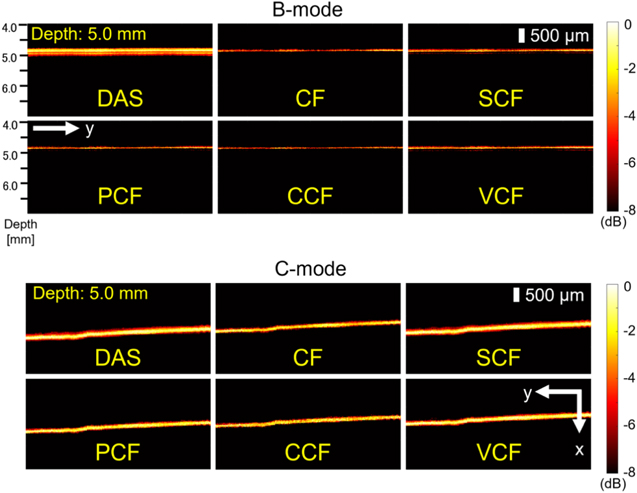

As one of the results of the phantom study, the images generated when the phantom was 5.0 mm away from the annular array are shown in Fig. 4. Figure 5 also shows the visualized phantom diameters in each MAP image of the phantom study visualized at all depths. Furthermore, Table I shows the sharpening ratio by applying each coherence factor method to the DAS beamformed signals.

Fig. 4. (Color online) The B-mode and C-mode images generated when the phantom was 5.0 mm away from the annular array.

In the B-mode image, the phantom image visualized with the DAS method was thicker than the original diameter, especially at depths of 5.0–6.5 mm, which was more than twice as thick as the original diameter of 100 μm. In contrast, all types of coherence factors showed a high effect of sharpening. However, in the case of the CCF method, the diameter of the phantom was thinner than 100 μm at all depths. At a depth of 7.0 mm, the diameter of the visualized phantom was thinner than the original diameter when several types of coherence factors were applied.

In the C-mode image, the phantom image visualized with the DAS method was thicker than the original diameter, which was more than twice as thick as the original diameter of 100 μm, similar to the B-mode. On the other hand, the effects of sharpening by all types of coherence factors were confirmed at all depths. The CCF method showed the highest sharpening effect as well as B-mode. However, the effect of sharpening by the SCF method was small than the other coherence factors. The width of the phantom visualized by C-mode tended to be thicker in the deeper position.